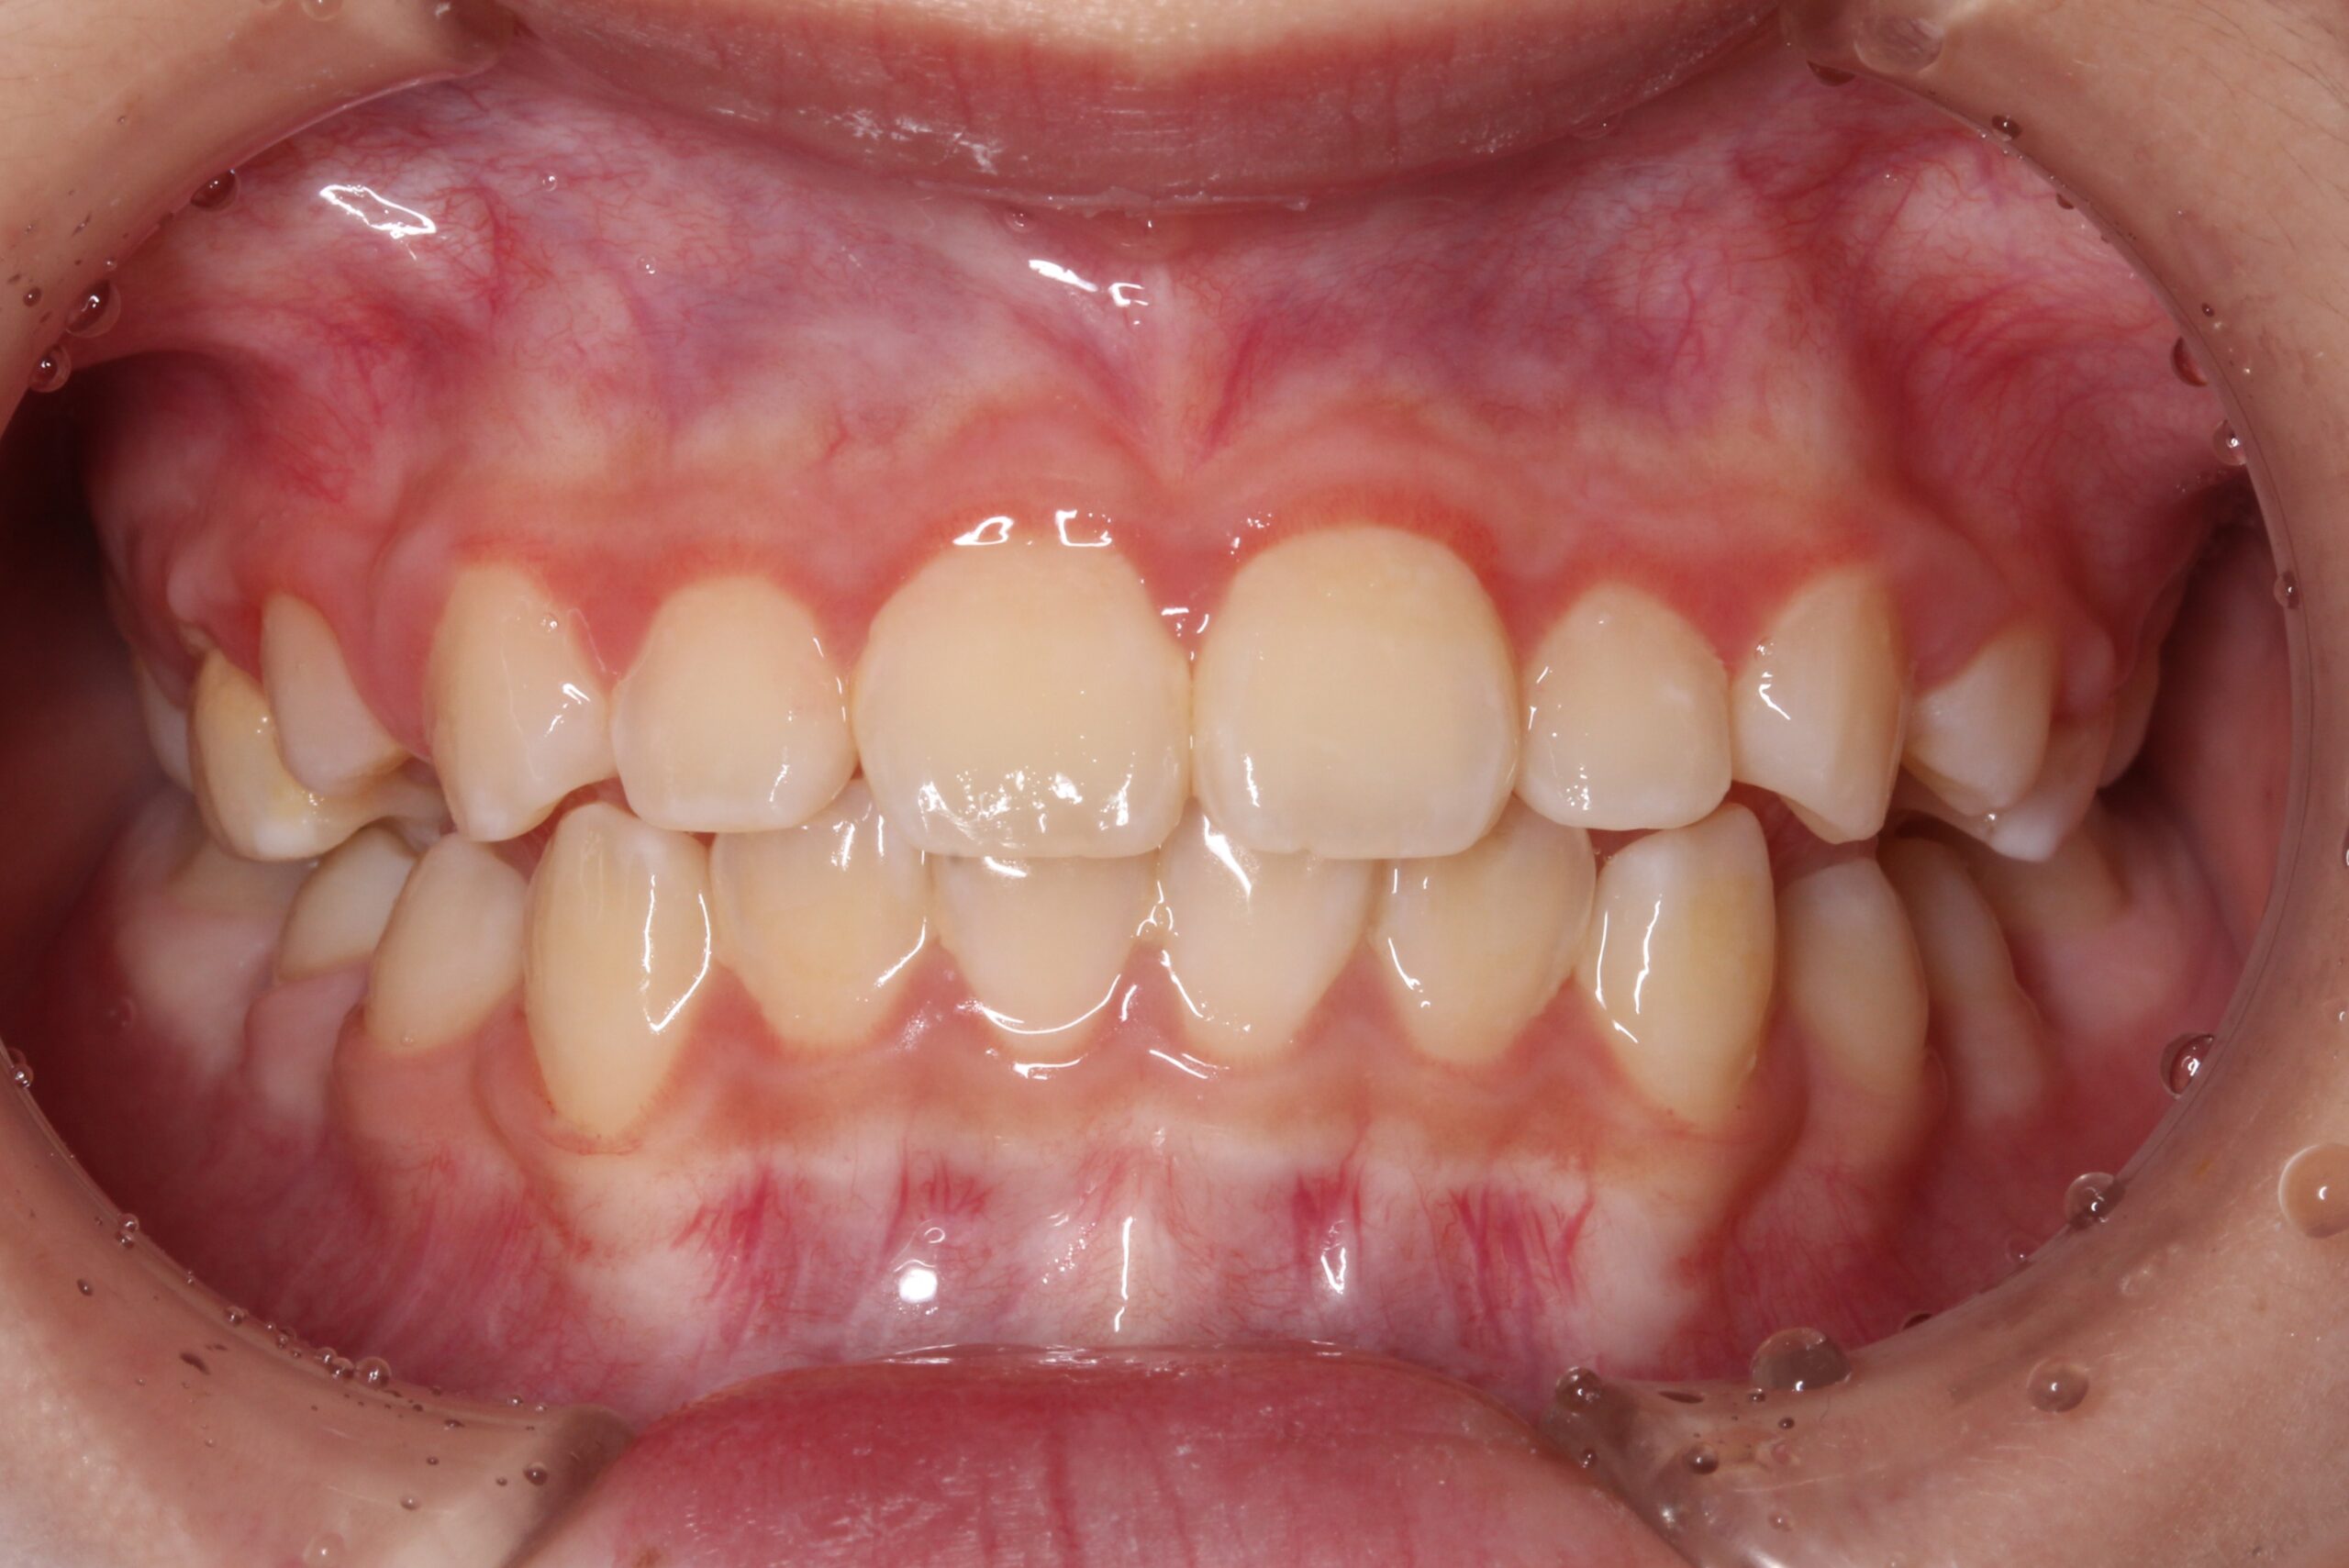

矯正術後:正面

| 治療期間 | ・マウスピース矯正:10カ月 |

| 治療費用 | 770,000円(税込) |

| 治療内容 | 患者様は全体的な歯並びのがたつきを気にされており、矯正検査後叢生Ⅰ級と診断いたしました。 |